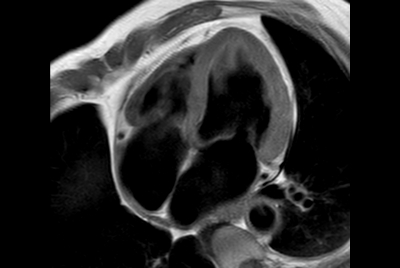

Knee ACL repair